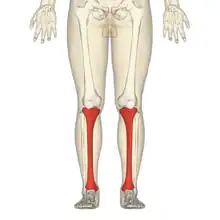

Skinneben

Skinnebenet (lat. tibia) er en rørknogle, der sammen med lægbenet udgør underbenets knogler. Tibia er den mediale af de to underbensknogler; tibia er betydelig tykkere og stærkere end fibula og bærer kroppens vægt. Tibia er efter lårbensknoglen (femur) kroppens største knogle. Proximalt er knoglen forbundet til knæleddet og lårbensknoglen, hvorimens den distalt artikulerer sig til fodens tarsalknogler.